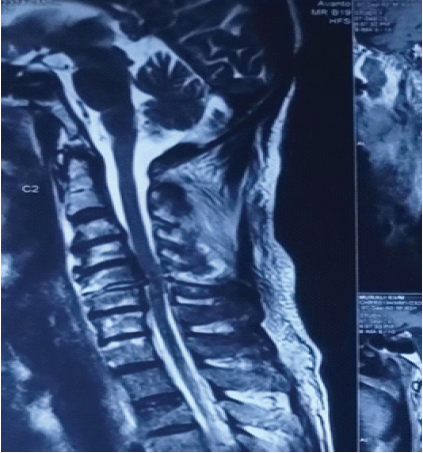

MRI sequences showed anterior dislocation of the C5 vertebral body over C6 vertebra, with bilateral locked facets, spinal cord compression, and signal intensity changes indicating cord edema (Fig. 4).

Figure 4: Magnetic resonance imaging sequences showing anterior dislocation of the C5 vertebral body over C6 vertebrae with bilateral locked facets, spinal cord compression, and signal intensity changes indicating cord edema.